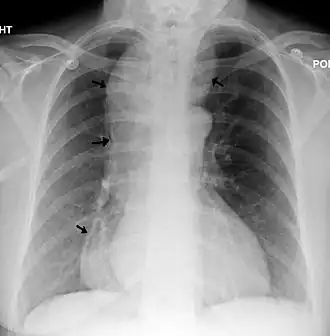

- Рентгенография с контрастированием пищевода барием.

- Эндоскопия пищевода и желудка. Особое внимание уделяется осмотру гастроэзофагеального перехода в тот момент, когда эндоскоп проходит через не расслабленный нижний пищеводный сфинктер.